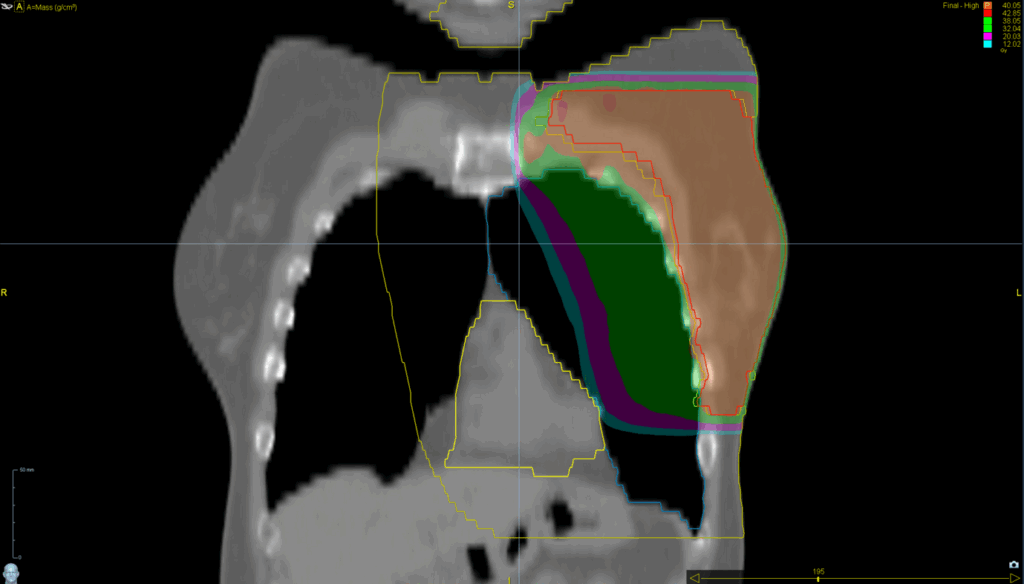

Treatment Plan Images

Fractionation / Protocol Used

40.05 Gy in 15 fractions

TomoDirect™ 2 angles

• VitalHold™

TomoEDGE™ 5cm

Planning Time Optimized with VOLO™ Ultra

20 min